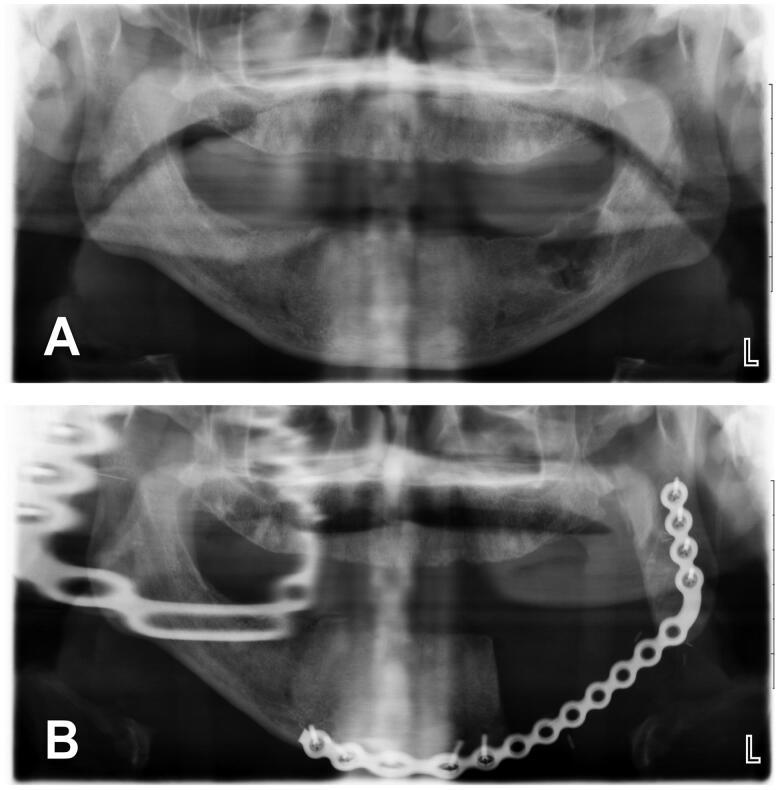

We studied 21 patients who underwent radical ameloblastoma excision followed by immediate reconstruction. Comorbidities, consumption of alcohol and/or tobacco and BMI status did not contribute to an unfavorable outcome. Giant ameloblastoma (≥5 cm) and/or tumor involving bony curvatures increased surgical complexity, the incidence of complications and hospital stay.

我们研究了21例接受成釉细胞瘤根治性切除并立即进行重建的患者。合并症、酒精和/或烟草消费以及体重指数状况并未导致不良预后。巨大成釉细胞瘤(≥5厘米)和/或累及骨弯曲的肿瘤增加了手术复杂性、并发症发生率和住院时间。